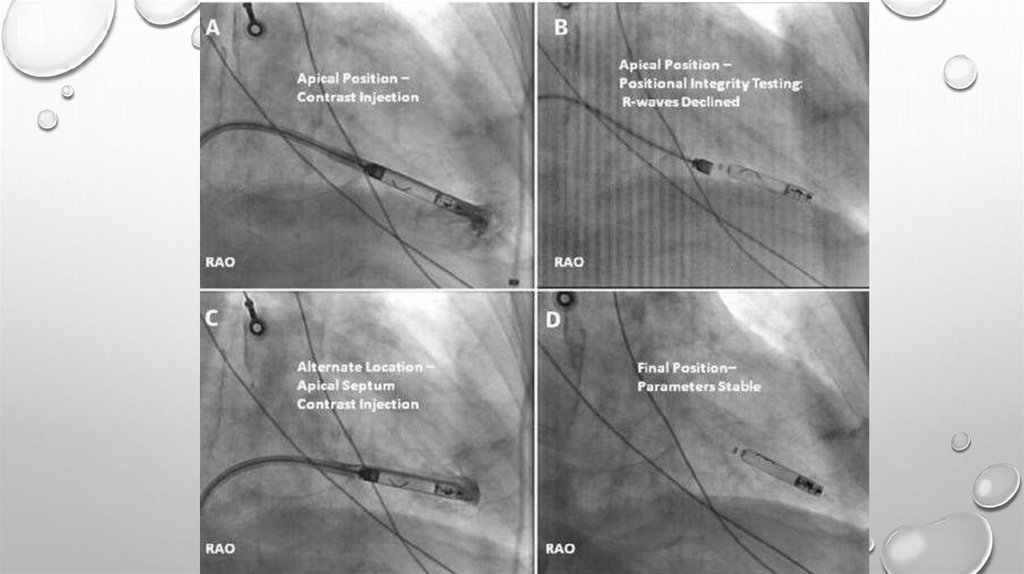

ТЕХНИКА ОПЕРАЦИИ